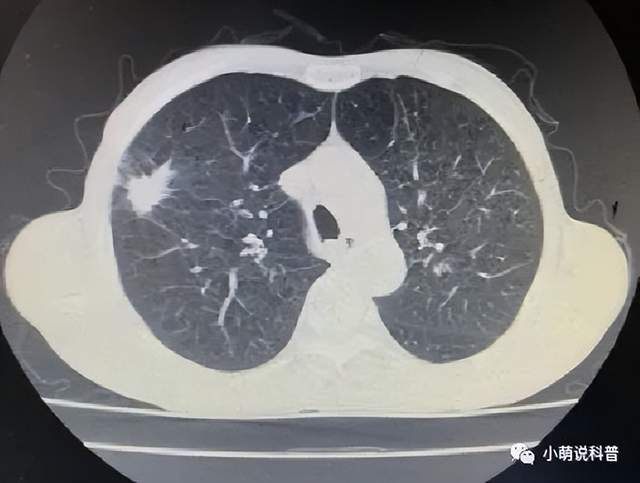

患者为57岁男性,因反复咳嗽、咳痰伴胸闷20余年,发现肺部结节1周在我院胸外一科住院治疗。入院后完善相关检查,胸部CT示双肺重度气肿,右肺上叶前段见形态不规则、直径约2.3㎝大小、边缘毛糙、可见毛刺的结节影,考虑肺占位性病变。

消融前肺部肿瘤

CT引导下经皮肺穿刺活检病理证实为右上肺鳞癌。患者肺功能FEV1:0.76L;FEV1占预计值:27.4%。血气分析示Ⅱ型呼吸衰竭。患者目前心肺功能差,经积极肺康复锻炼,患者肺功能仍无改善。考虑患者无法耐受常规的手术及放化疗,肿瘤分子检测无靶向及免疫治疗指征。